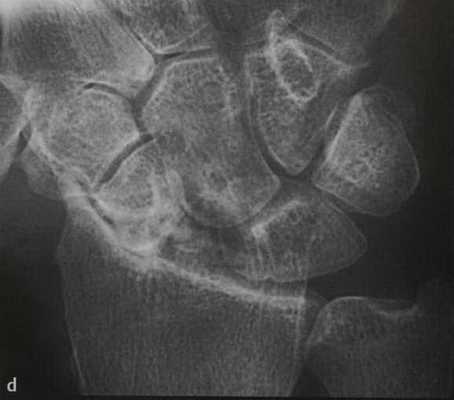

а-d Перелом ладьевидной кости. МРТ. (а) Неконтрастное Т1-взвешенное изображение демонстрирует распространенные участки снижения интенсивности сигнала.

(d) Длительно существующий некроз ладьевидной кости с резорбцией проксимального фрагмента, дегенеративными изменениями, поражающими лучезапястный сустав с нестабильностью запястья и уменьшением высоты запястья.